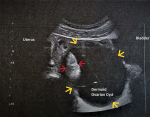

Diagnostic assessment: transabdominal ultrasound in the anatomical position of the right ovary revealed a unilocular, well-circumscribed cystic mass with a maximum diameter of about 105 mm. Solid components were observed within the cystic mass (Figure 1). The left ovary was normal. No pathology from the uterus was found. Urgent blood tests of our patient revealed Ht 38.6%, Hb 13.4gr/dl, PLT 234x103/ml, WBC 10.38x103/ml, NEUT 78.6%. C-reactive protein, coagulation, and biochemical tests were within normal range.

Early preoperative diagnosis of adnexal torsion with an ovarian dermoid cyst is very important. For optimal management of the condition, a diagnostic strategy that includes multiple imaging techniques such as ultrasound, computed tomography, and magnetic resonance imaging is necessary. Ultrasound is currently the most common and widely available imaging for the preoperative evaluation of ovarian dermoid cysts. It is currently considered that the acute symptomatology of patients in the emergency department combined with ultrasound findings contributes significantly to accurate diagnosis of adnexal torsion with the presence of a mature ovarian cystic teratoma. In our patient, the characteristic ultrasound feature of solid components within the well-circumscribed cystic mass (Figure 1), combined with acute abdominal pain, multiple vomiting, and the young age of the patient, established the diagnosis of twisted mature ovarian cystic teratoma. Early diagnosis, based only on clinical and ultrasound findings, contributed significantly to the timely surgery and the preservation of the ovary and fallopian tube in our patient. On ultrasound imaging, the presence of a dermoid plug of variable size, with one or more highly echogenic nodules within the cyst or atypical only within the wall of the cystic mass, advocates the diagnosis of mature cystic teratoma. Also, a fat-fluid level or a distinct echogenic focus indicating the presence of an ectopic tooth is a strong ultrasound feature for the diagnosis of teratoma. Ultrasound diagnosis of ovarian dermoid cysts can be based on transabdominal ultrasound with pelvic imaging [5]. In our patient, the diagnosis was based exclusively on transabdominal ultrasound. No transvaginal ultrasound was performed because the patient was a virgin

Figure 1: transabdominal ultrasound imaging of a twisted dermoid ovarian cyst (yellow arrows) with the typical presence of fat within it (red arrows)